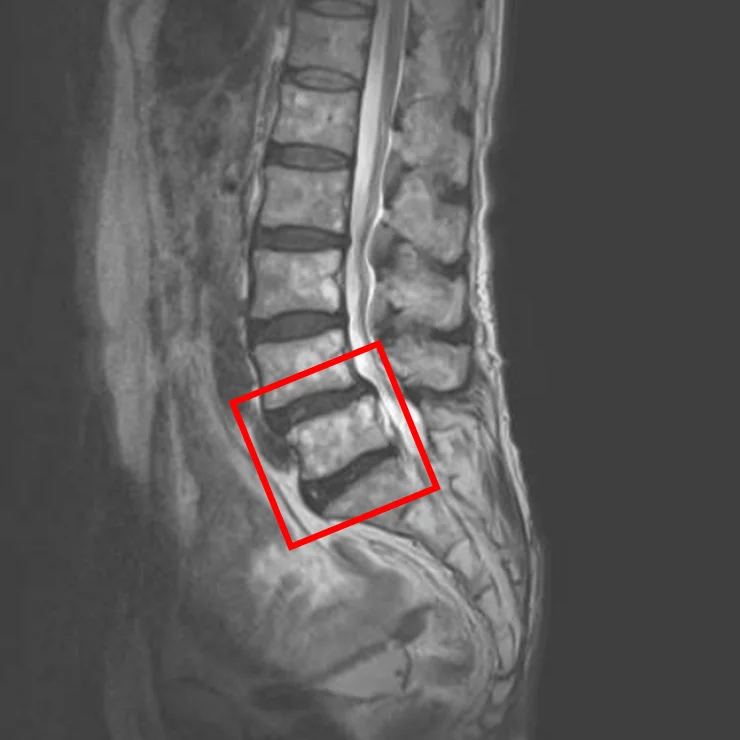

По данным МРТ и результатам осмотра пациента выявлена дегенерация межпозвоночных дисков L4/L5, L5/S1, а также спондилолистез L4 и стеноз межпозвонковых отверстий L4/L5, L5/S1.

Симптомы по 10-балльной шкале (0 – отсутствие симптомов, 10 – сильные боли/онемение):

– боли в пояснице: 5;

– боли в ногах: 5;

– онемение в ногах: 5;

– боли в ягодицах: 4.